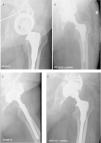

Paciente de 40 años con artritis reumatoide en el cual se implantó una prótesis total de cadera primaria en 2003; posteriormente precisó recambio de cotilo con injerto óseo por aflojamiento aséptico en 2008; en 2010 necesitó otro recambio de cotilo con injerto óseo e implantación de un anillo de refuerzo tipo Bat-Cup por aflojamiento aséptico con protrusión acetabular, el cual también fracasó en 2012 con rotura del implante y aflojamiento aséptico, motivo por el cual se colocó el Cup-Cage. En las imágenes A y B se muestran las radiografías en las proyecciones anteroposterior y axial, respectivamente, donde se puede observar el aflojamiento acetabular con rotura de la inserción isquiática del anillo. Las imágenes C y D corresponden al control radiográfico en las proyecciones axial y anteroposterior a los 3 años y medio de la implantación del Cup-Cage, con una correcta integración del injerto acetabular y una buena posición del implante.